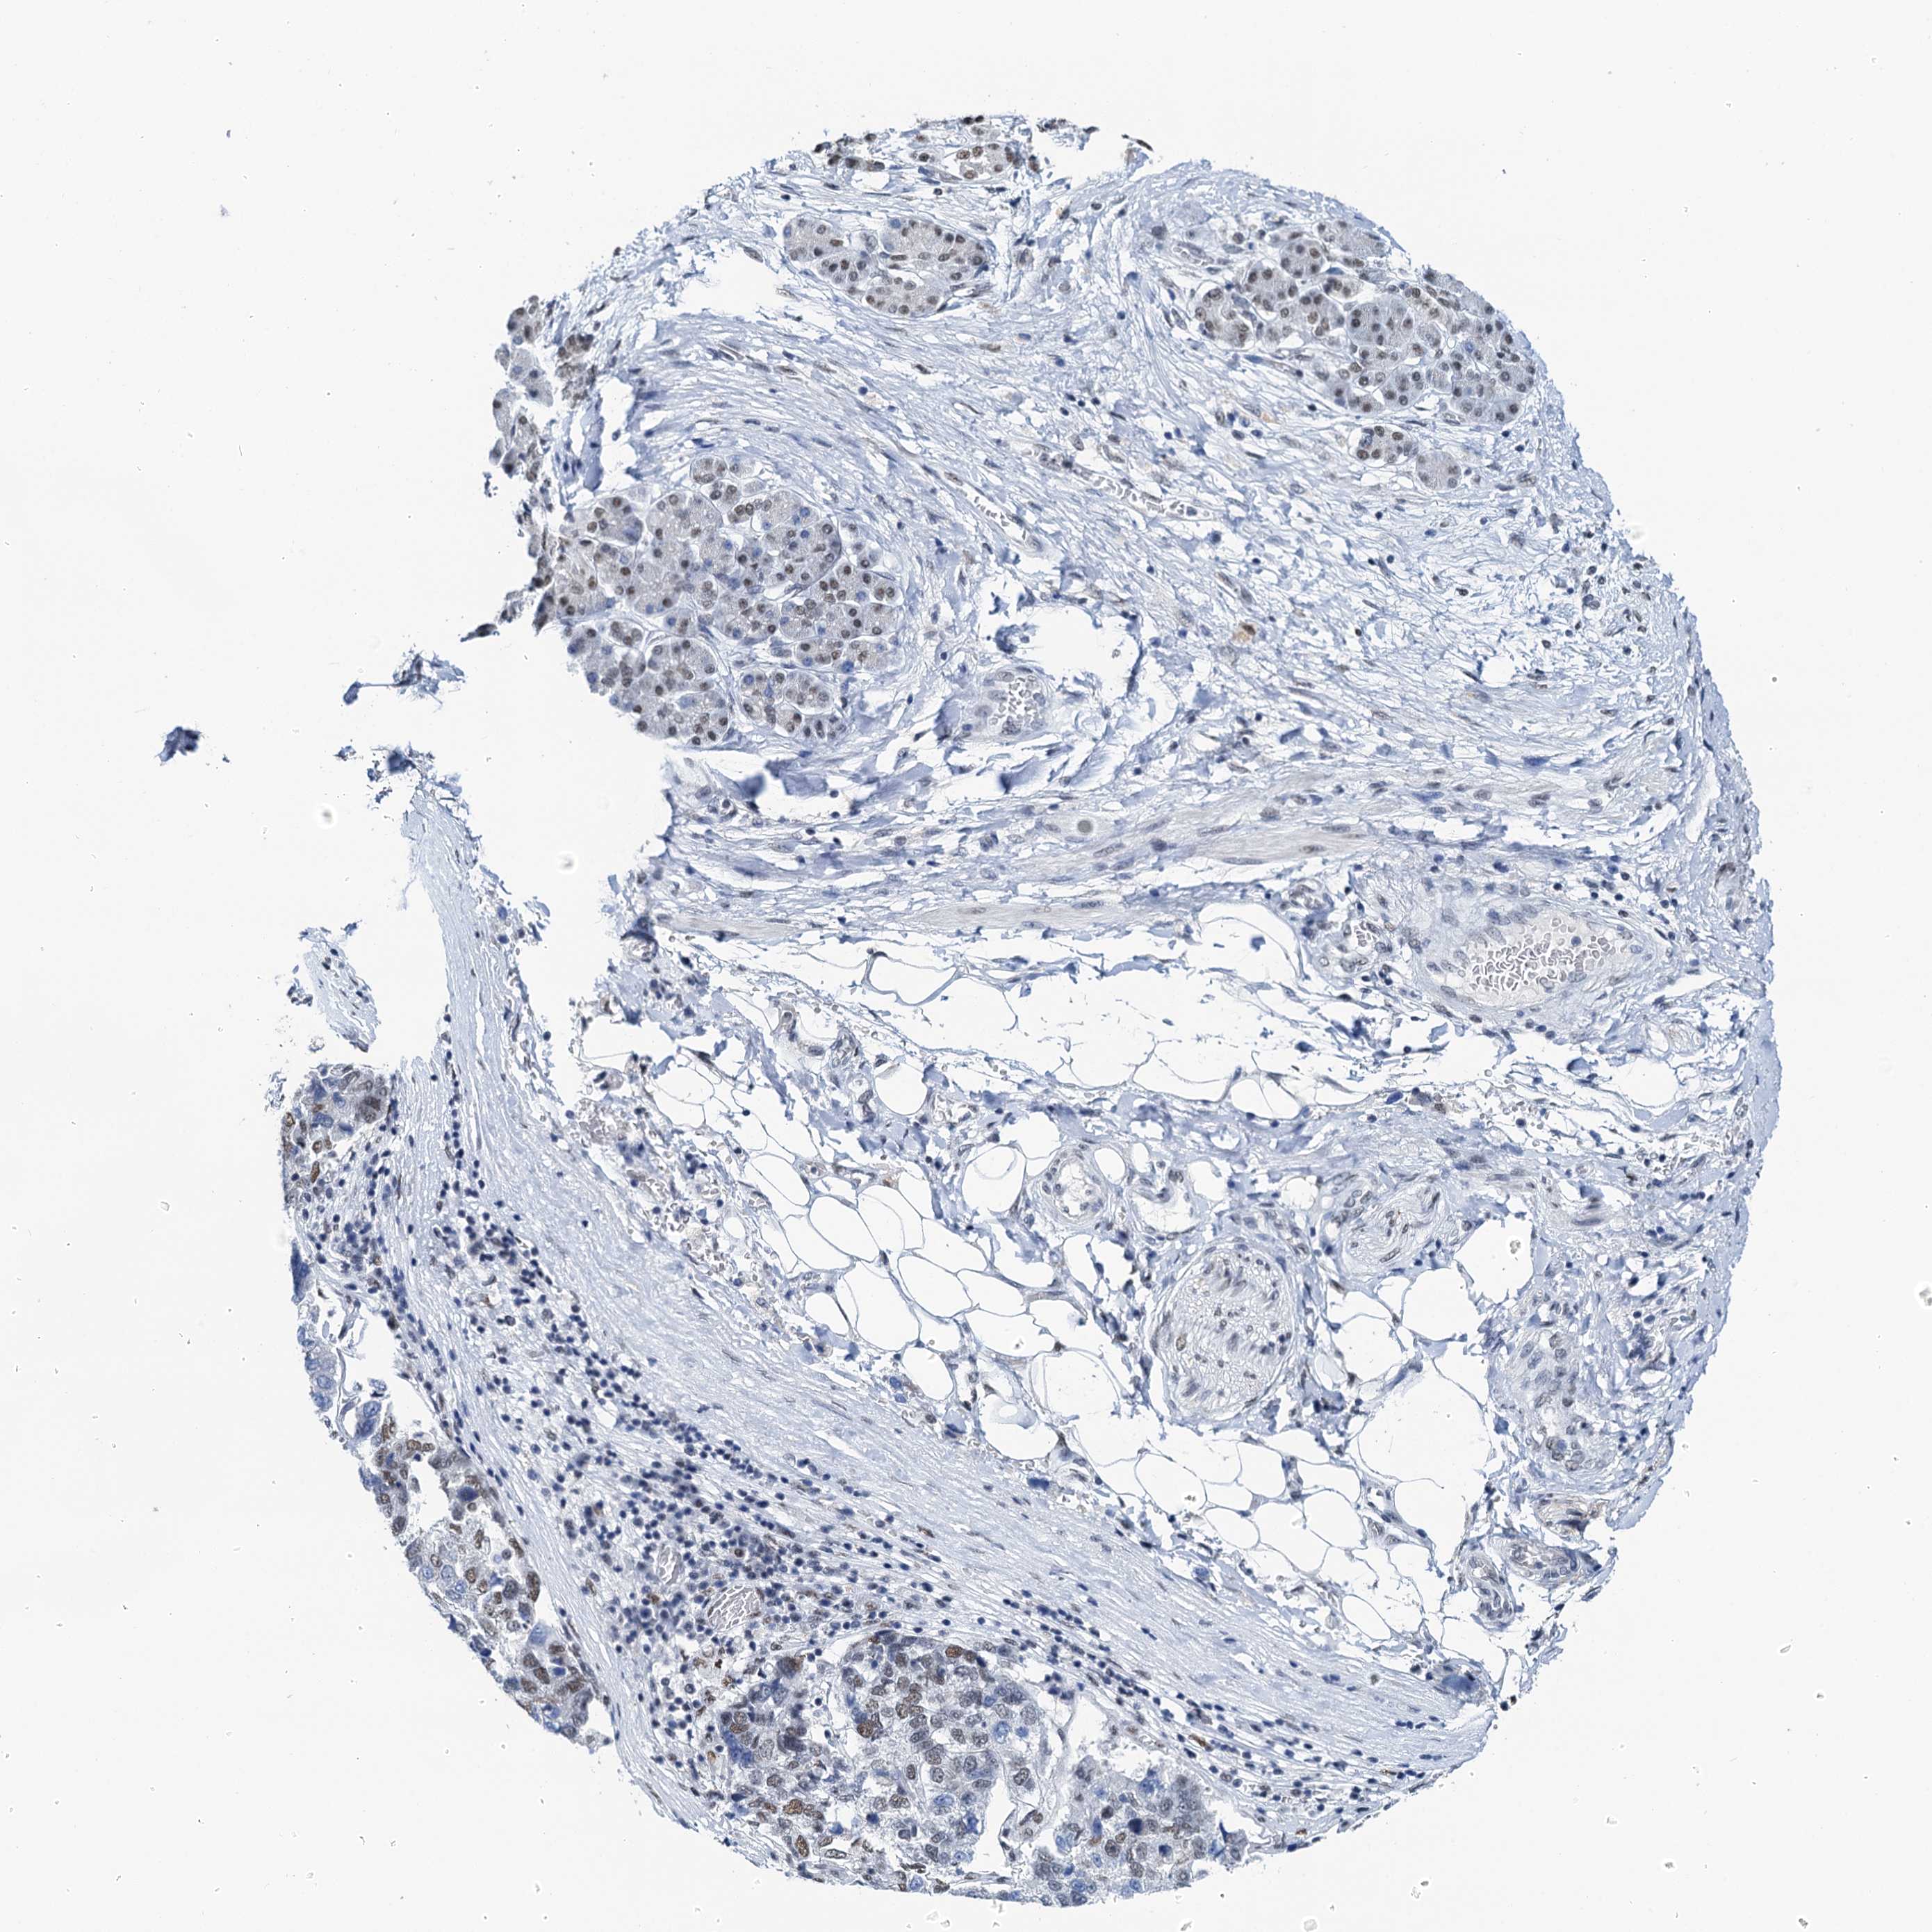

PANCREATIC CANCER - Protein expressioni

A mouse-over function shows sample information and annotation data. Click on an image to view it in a full screen mode. Samples can be filtered based on level of antibody staining by selecting one or several of the following categories: high, medium, low and not detected. The assay and annotation is described here.

Note that samples used for immunohistochemistry by the Human Protein Atlas do not correspond to samples in the TCGA dataset.

Antibody stainingi

Antibody staining in the annotated cell types in the current human tissue is reported as not detected, low, medium, or high, based on conventional immunohistochemistry profiling in selected tissues. This score is based on the combination of the staining intensity and fraction of stained cells.

Each image is clickable and will lead to virtual microscopy that enables deeper exploration of all samples and also displays staining intensity scores, fraction scores and subcellular localization as well as patient and tissue information for each sample.

Antibody HPA040256

Antibody HPA040381

Staining

High

Medium

Low

Not detected

Intensity

Strong

Moderate

Weak

Negative

Quantity

>75%

75%-25%

<25%

None

Location

Nuclear

Cytoplasmic/membranous

Cytoplasmic/membranous,nuclear

Adenocarcinoma, NOS